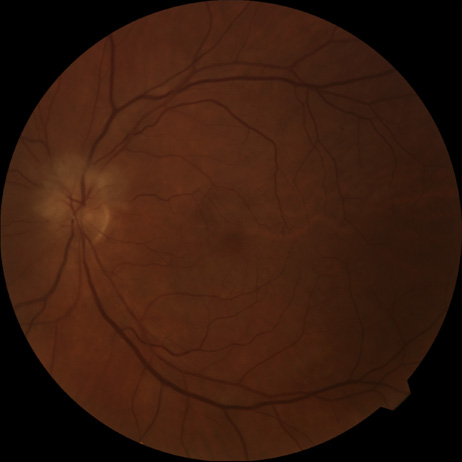

When a branch retinal artery is obstructed, there is usually whitening of the retina in the area supplied by the artery (Fig. 2). In most eyes (62% in one series), emboli are responsible for the obstruction.94 The temporal branch arteries are involved in almost all cases that have been reported,92,94 but whether this is because nasal branch retinal artery obstructions are rare or because such obstructions are simply asymptomatic is unknown. The characteristics of a branch retinal artery obstruction on intravenous fluorescein angiography are similar to those for central retinal artery obstruction.